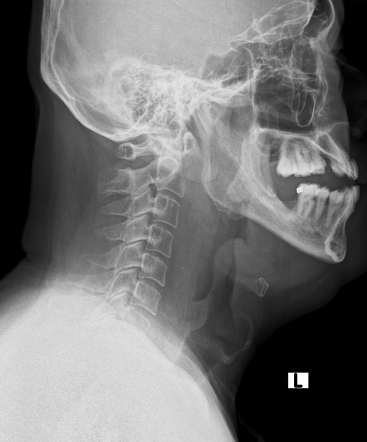

진단: 특징적인 임상증상 및 경부 전면/측면 X선 촬영

경부 AP X-ray 촬영: 성문하 부위가 좁아져 보이는 '첨탑 징후'(steeple sign)가 특징

lateral Xray: distended hypopharynx, subglottic edema